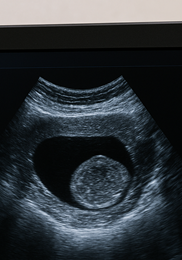

가장 기본적인 검사는 골반 초음파입니다. 복부 또는 질 초음파로 근종의 위치, 크기, 개수를 확인합니다. 필요시 MRI로 더 세밀하게 구조를 파악하며, 출혈이나 생리 이상이 심하면 자궁내시경을 통해 점막 상태를 직접 확인합니다. 자궁근종 증상이 경미하더라도 주기적으로 검사해야 크기 변화를 조기에 파악할 수 있습니다.